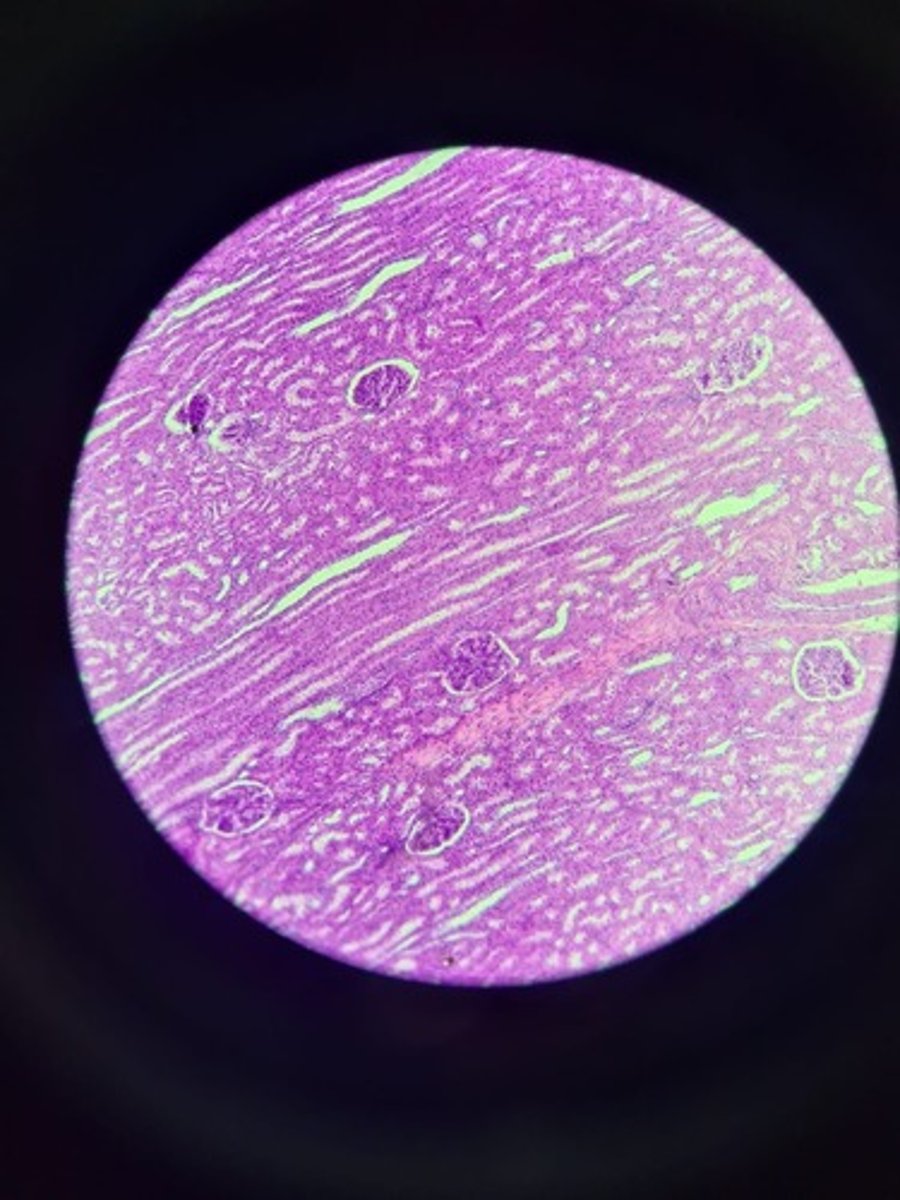

Kidney HE

Kidney HE

Kidney HE

Kidney HE

Kidney HE